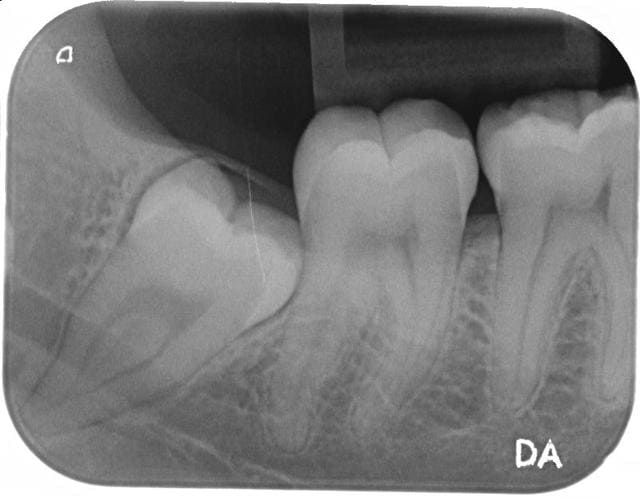

Pourquoi? le trajet du nerf n est pas devie par les racines. il se trouve juste superpose sur la radio.

"Pourquoi? le trajet du nerf n est pas devie par les racines. il se trouve juste superpose sur la radio."

A la vue de ces arguments, je te déconseille aussi l'extraction de cette dent.

Un cone beam ou scanner est indispensable avant l'intervention, surtout en cas de problème ensuite. Obligation de moyens.

Par sécurité je ferai aussi un scan ou un cone beam mais elle n'a pas l'air trop méchante.

Il n'y a pas de discontinuité de la lamina dura donc on peut penser qu'il s'agit bien d'une superposition mais sur une seule rétro alvéolaire c'est un peu juste.

Y a pleins d'études concernant les hypoesthesies post op dds qui l'ont montré, il y a des signes pano qui sont 'fiables' et prédictif d'un evenuel trouble neurologique post op:

Rétrécissement du canal

Effacement de la cortical du canal

Zone radio claire à l'apex de la dent (=les racines plongent dans le.canal)

Etc... Et ici rien de tout ça!